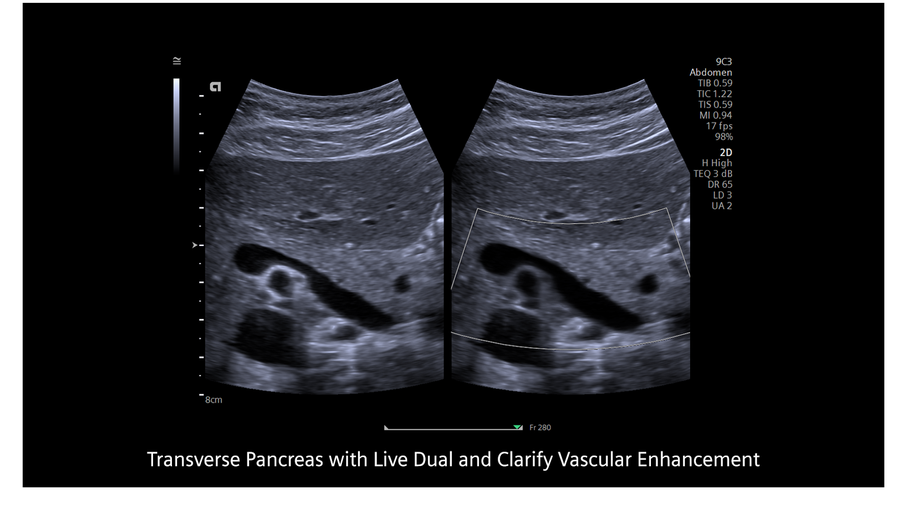

Кроме новой техники, можно заказать восстановленные медицинские системы: ультразвуковые сканеры, томографы, флюороскопы, ангиографы и хирургические установки С-дуга.